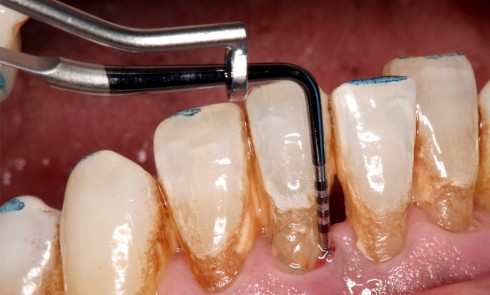

Odontologie restauratrice

Article réservé à nos abonnés L’inlay-core soumis au principe de la dentisterie fondée sur les preuves

Avec les progrès de la dentisterie adhésive et mini-invasive, des matériaux polymères, des techniques de collage, avec l’évolution des consciences...